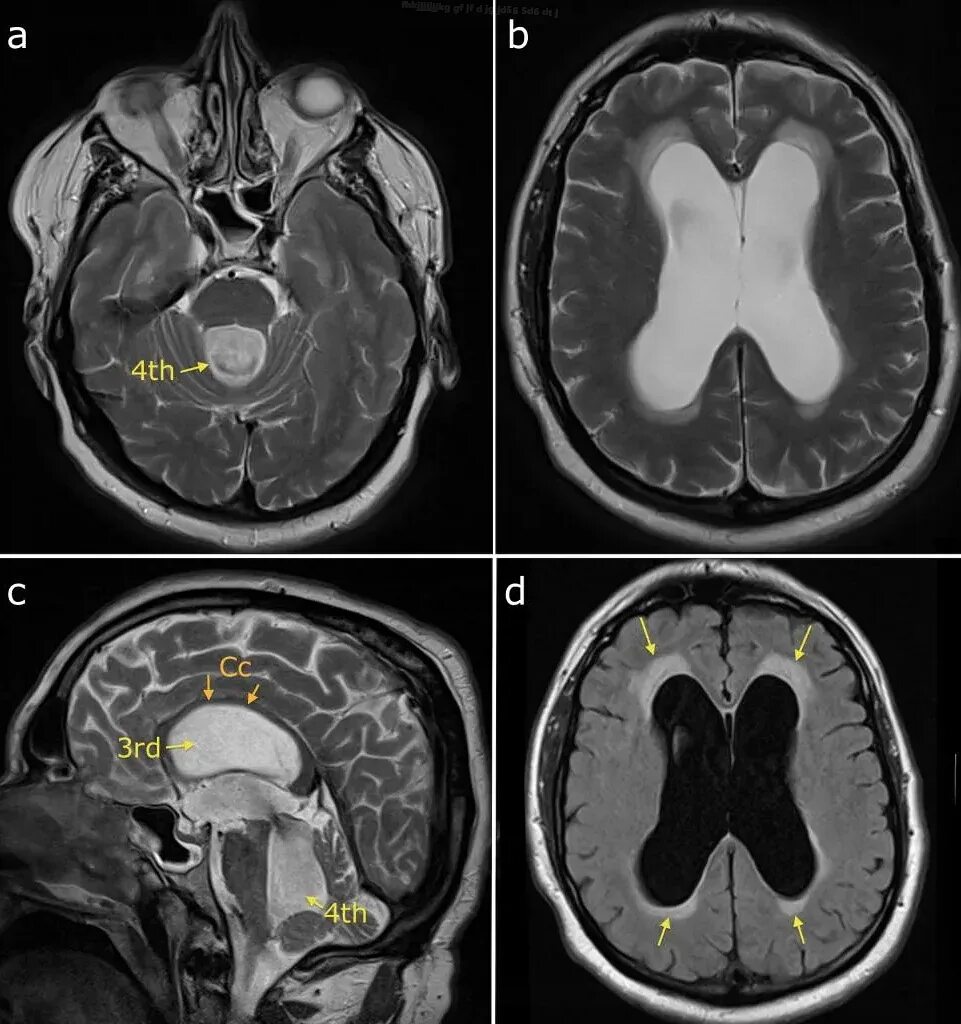

Расширение ликворосодержащих пространств